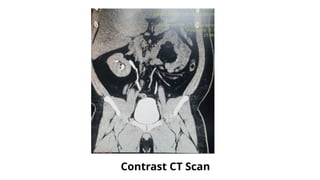

Contrast CT Scan